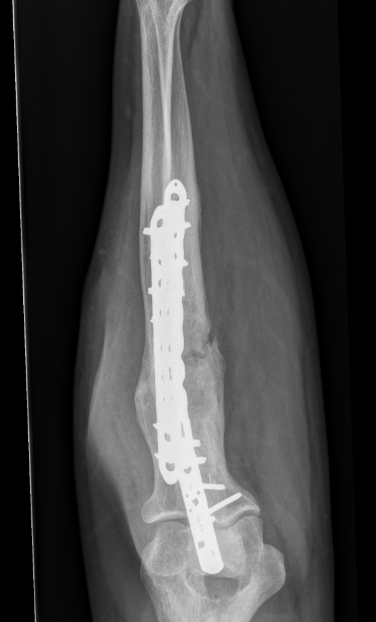

Radial fracture malunion requiring corrective osteotomy